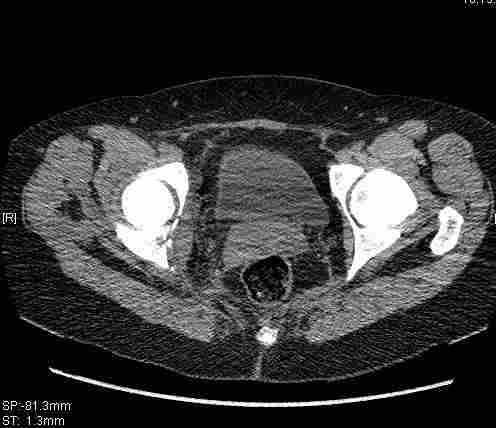

Удалось сегодня вывести пациентку в соседнюю больницу, где есть кт. Срезы сделаны только горизонтальные.

Приветствую,Антон.Рункова рядом нет,но после полученных данных КТ,обсуждали совместно.Итог обсуждения-развернутый ответ дать не получится,т.к.срезы выбраны не информативные.Если ориентироваться на данные 3D,то ,ИМХО,можно лечить на вытяжении.

Спасибо, Салават и коллеги. Насколько я понял,нужны срезы в сагитальной и фронтальной плоскостях?